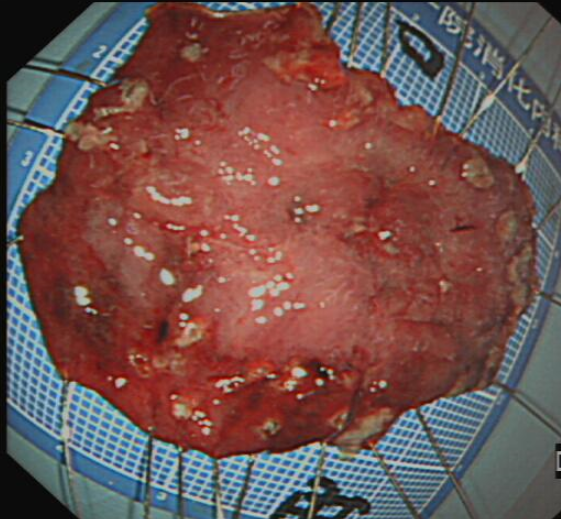

图4术中内镜剥离病变标本

术后病理报告 (胃角)腺体高级别异型增生,局灶癌变(黏膜内),切缘未见病变,病变已被完整切除。患者术后恢复良好,三日后顺利出院。此次手术的成功,为早期胃癌患者减少了痛苦,提高了生活质量。